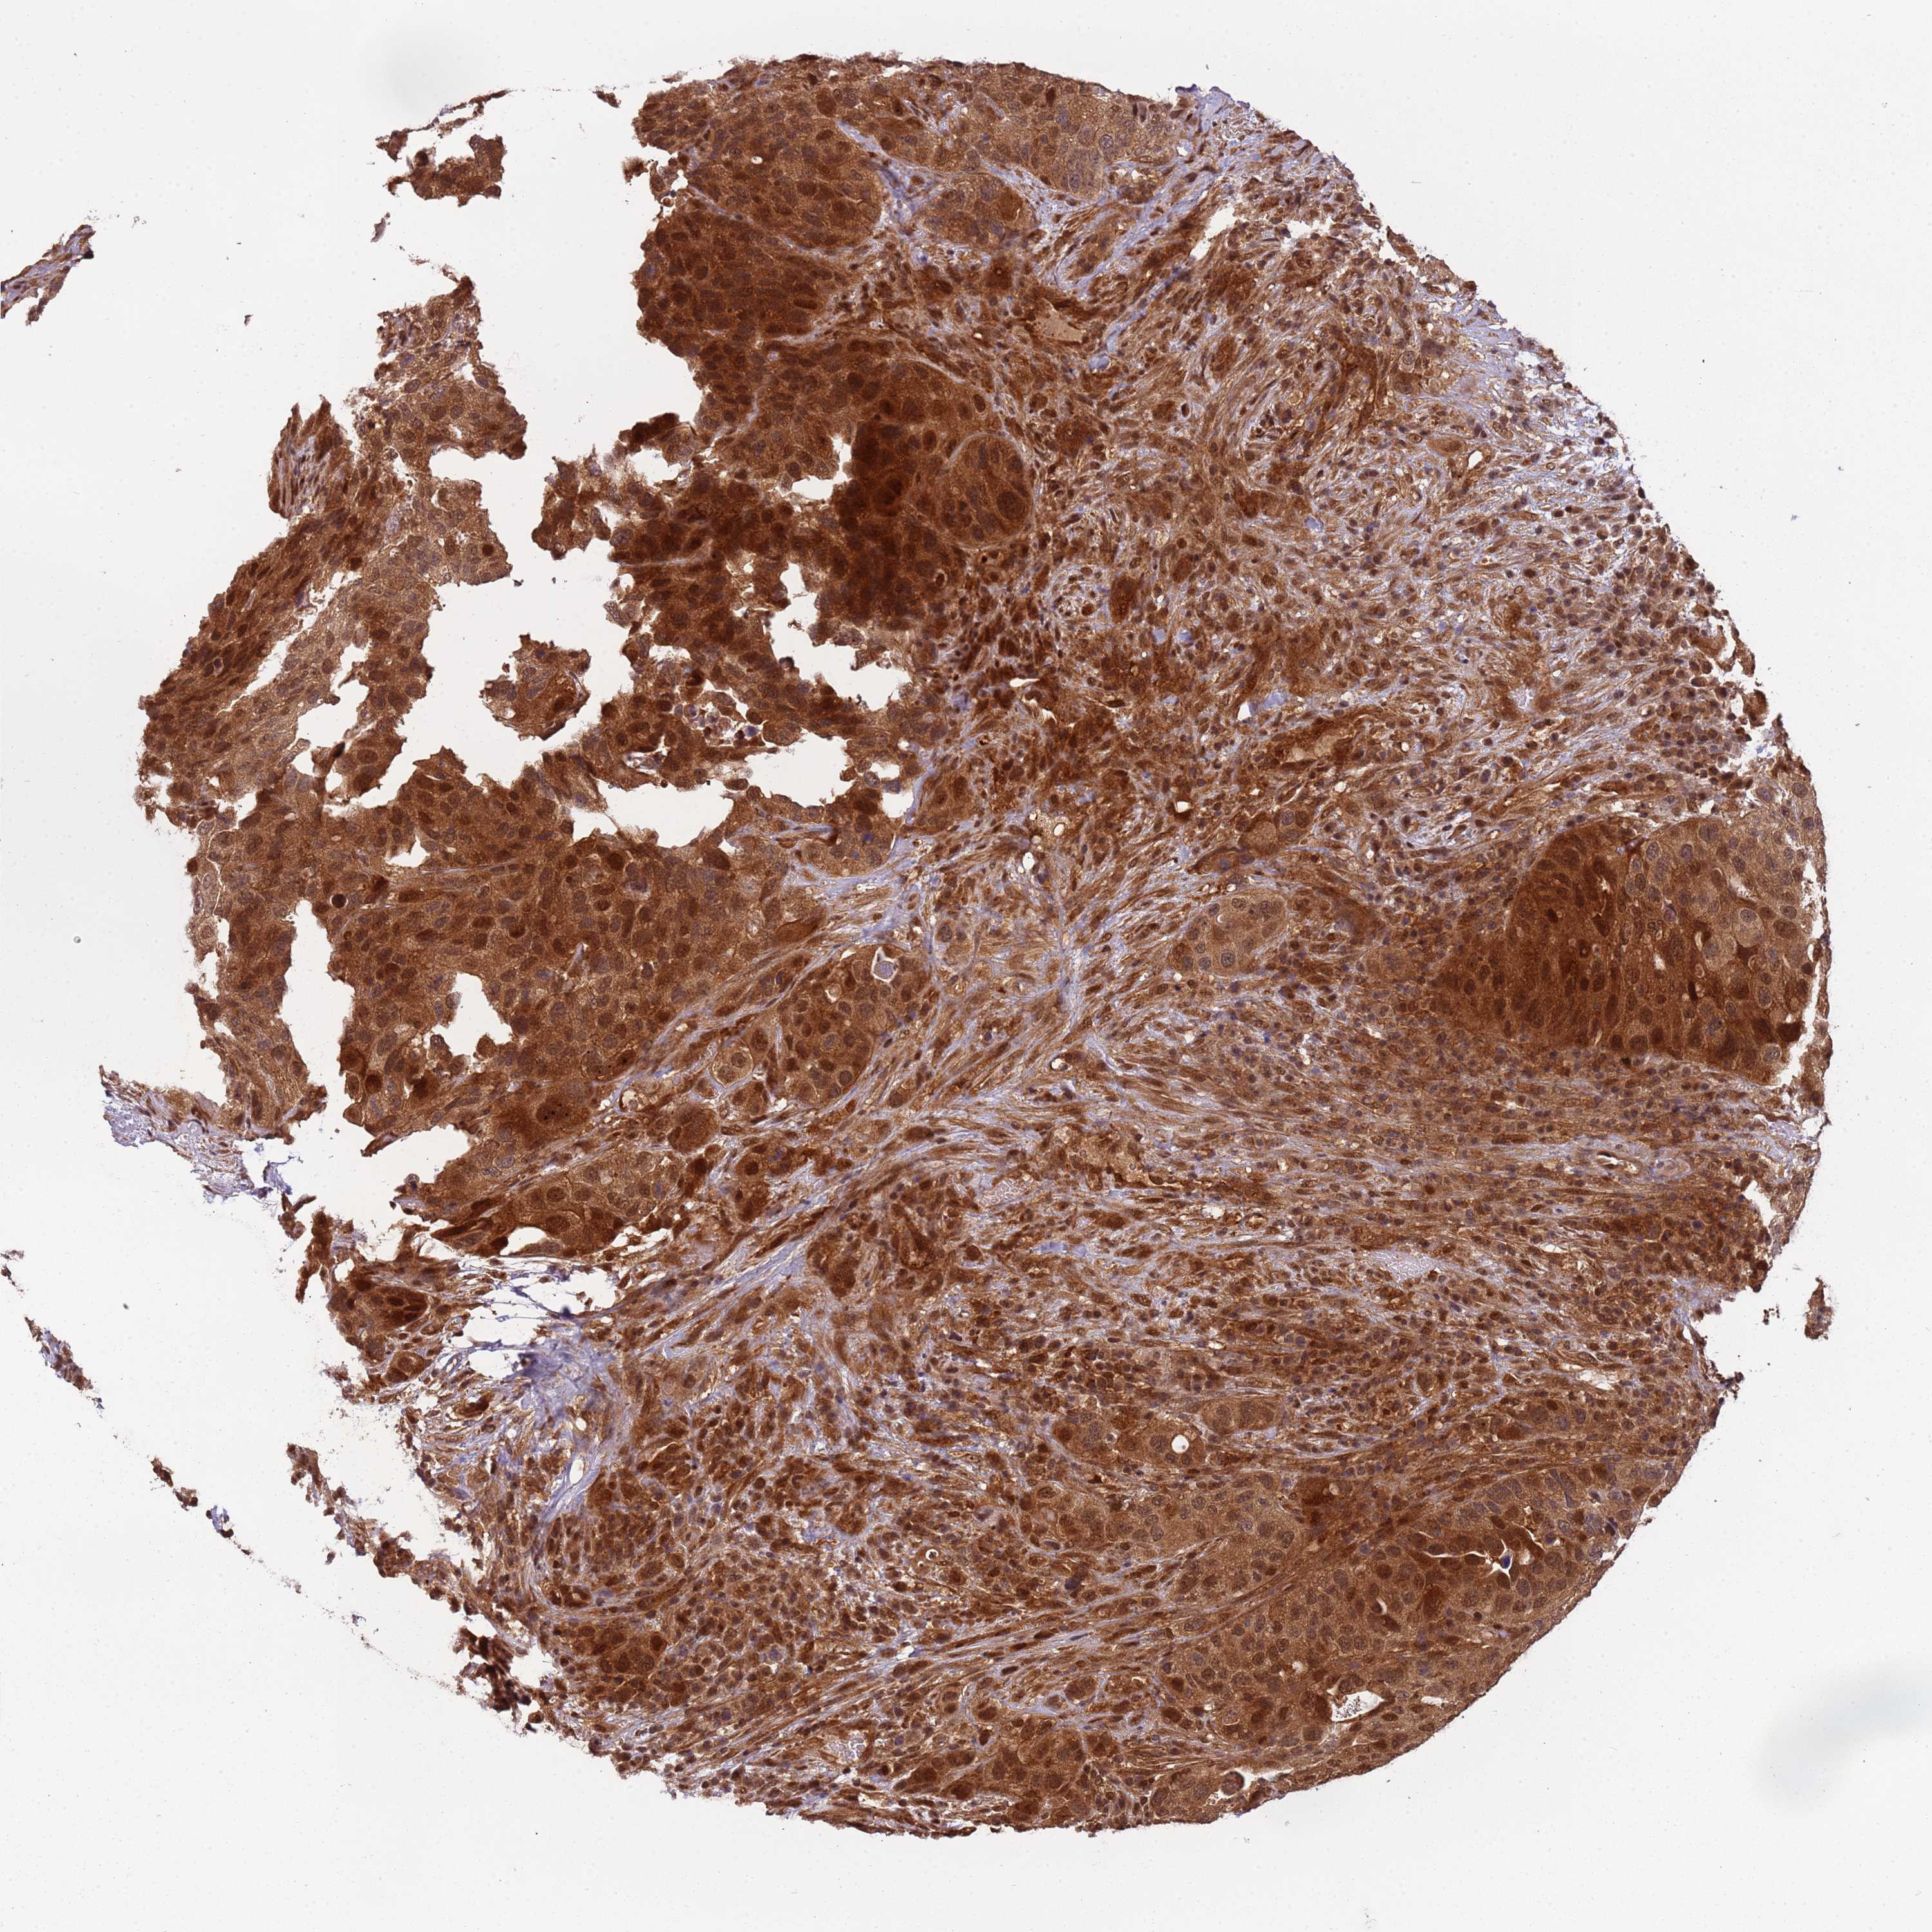

UROTHELIAL CANCER - Protein expressioni

A mouse-over function shows sample information and annotation data. Click on an image to view it in a full screen mode. Samples can be filtered based on level of antibody staining by selecting one or several of the following categories: high, medium, low and not detected. The assay and annotation is described here.

Antibody stainingi

Antibody staining in the annotated cell types in the current human tissue is reported as not detected, low, medium, or high, based on conventional immunohistochemistry profiling in selected tissues. This score is based on the combination of the staining intensity and fraction of stained cells.

Each image is clickable and will lead to virtual microscopy that enables deeper exploration of all samples and also displays staining intensity scores, fraction scores and subcellular localization as well as patient and tissue information for each sample.

Antibody HPA040744

Antibody HPA042032

Staining

High

Medium

Low

Not detected

Intensity

Strong

Moderate

Weak

Negative

Quantity

>75%

75%-25%

<25%

None

Location

Nuclear

Cytoplasmic/membranous

Cytoplasmic/membranous,nuclear

Urothelial carcinoma, High grade